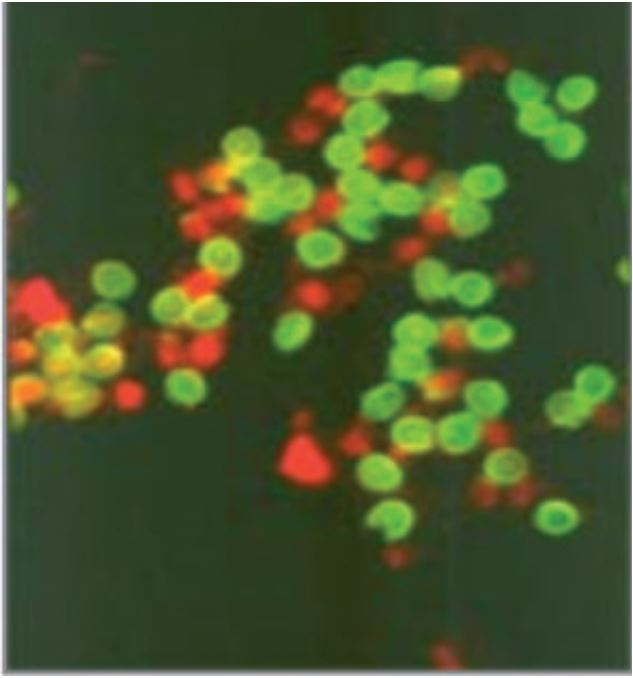

- Fig. 1. Crptoyporidium